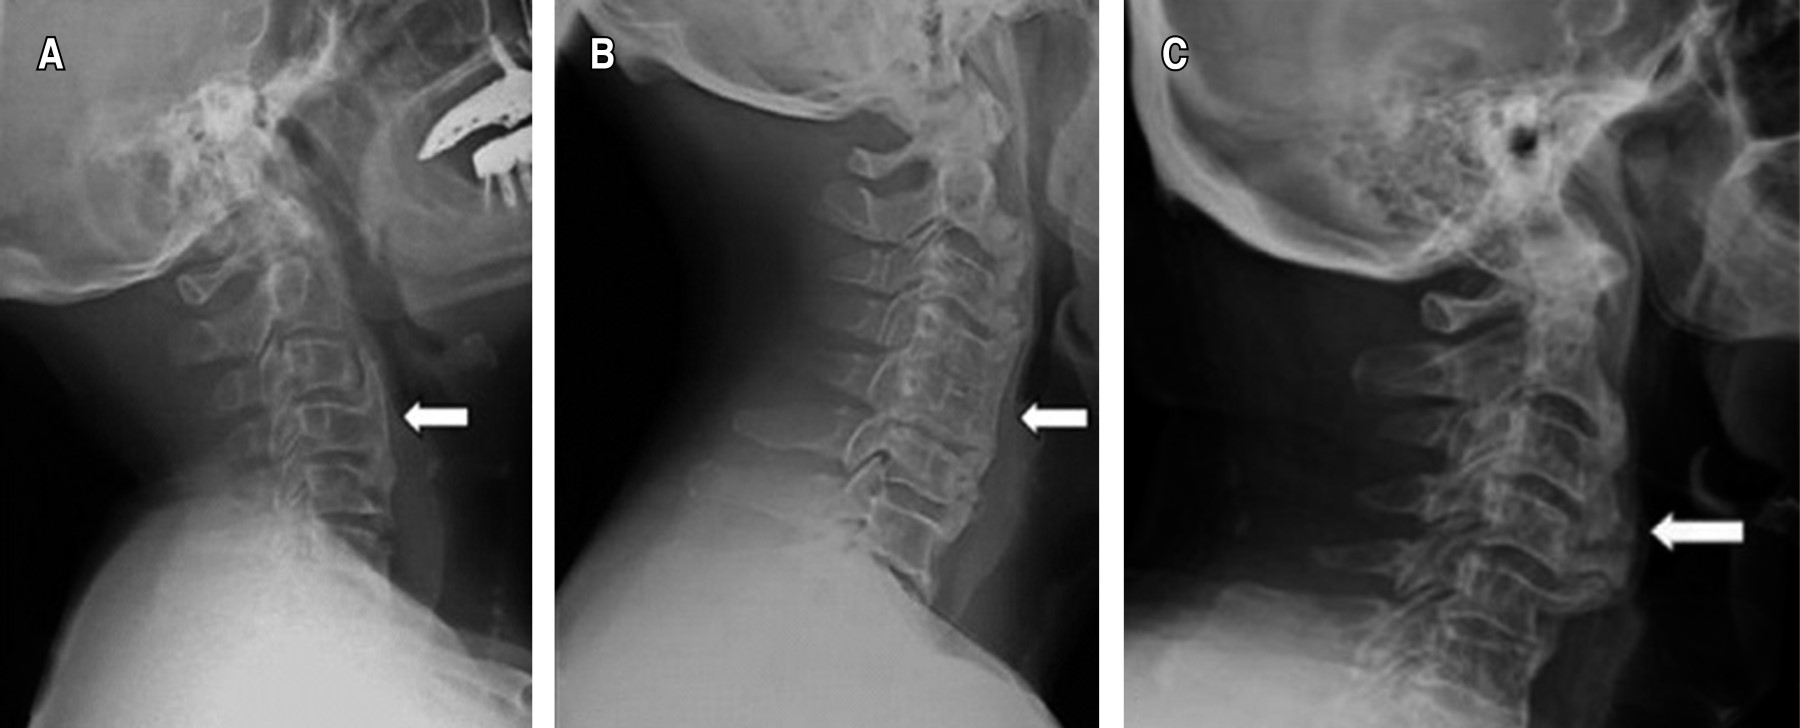

Dentro de las características radiográficas para diagnosticar DISH se pueden encontrar criterios de diversos autores. Sin embargo, en la actualidad prevalecen los de Resnick-Niwayama, aunque estos criterios se limitan a identificar pacientes en la etapa avanzada de la enfermedad (Tabla 1).13

Se pueden identificar diferentes signos en los estudios de imagen que pueden orientar al diagnóstico de DISH antes de que avance más la enfermedad. En un inicio el proceso de hiperostosis se desarrolla en la plataforma inferior del cuerpo anterior de la vértebra dando como resultado el signo "de la gota que cae" (Figura 1).14

Posteriormente el tejido óseo crece formando espolones o entesofitos y se expanden a la plataforma superior del cuerpo, formando así los característicos puentes intervertebrales y otros signos como "cera de vela derretida" y "pico de loro" (Figuras 2 y 3).14